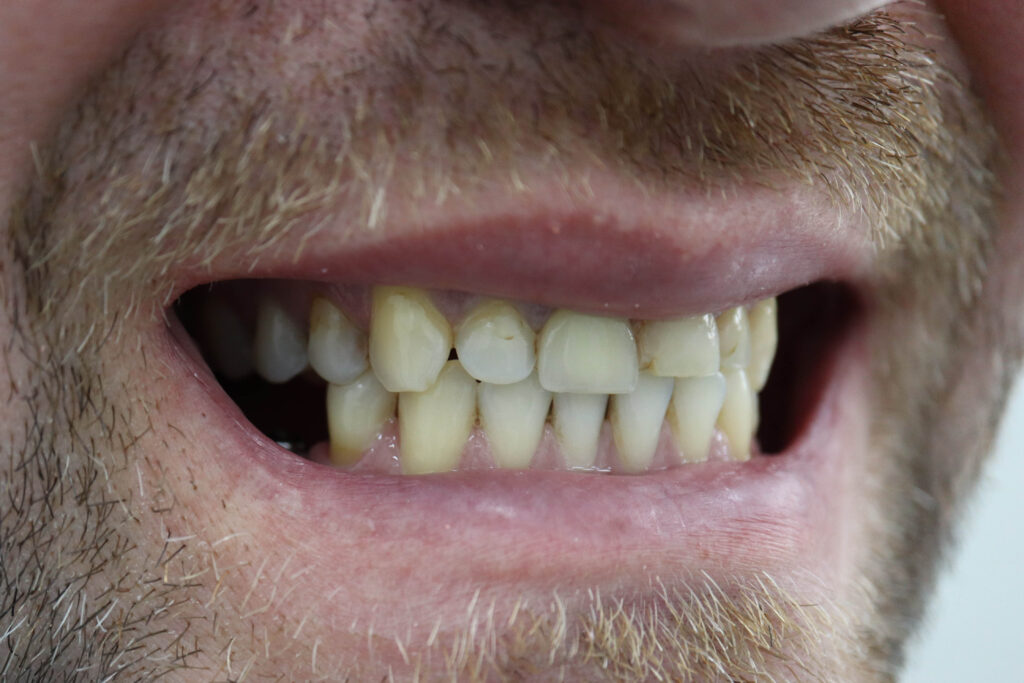

Ситуация до лечения

Пациент обратился с жалобами на эстетические недостатки.

Диагноз: Частичная адентия

Ситуация до лечения Бутримович